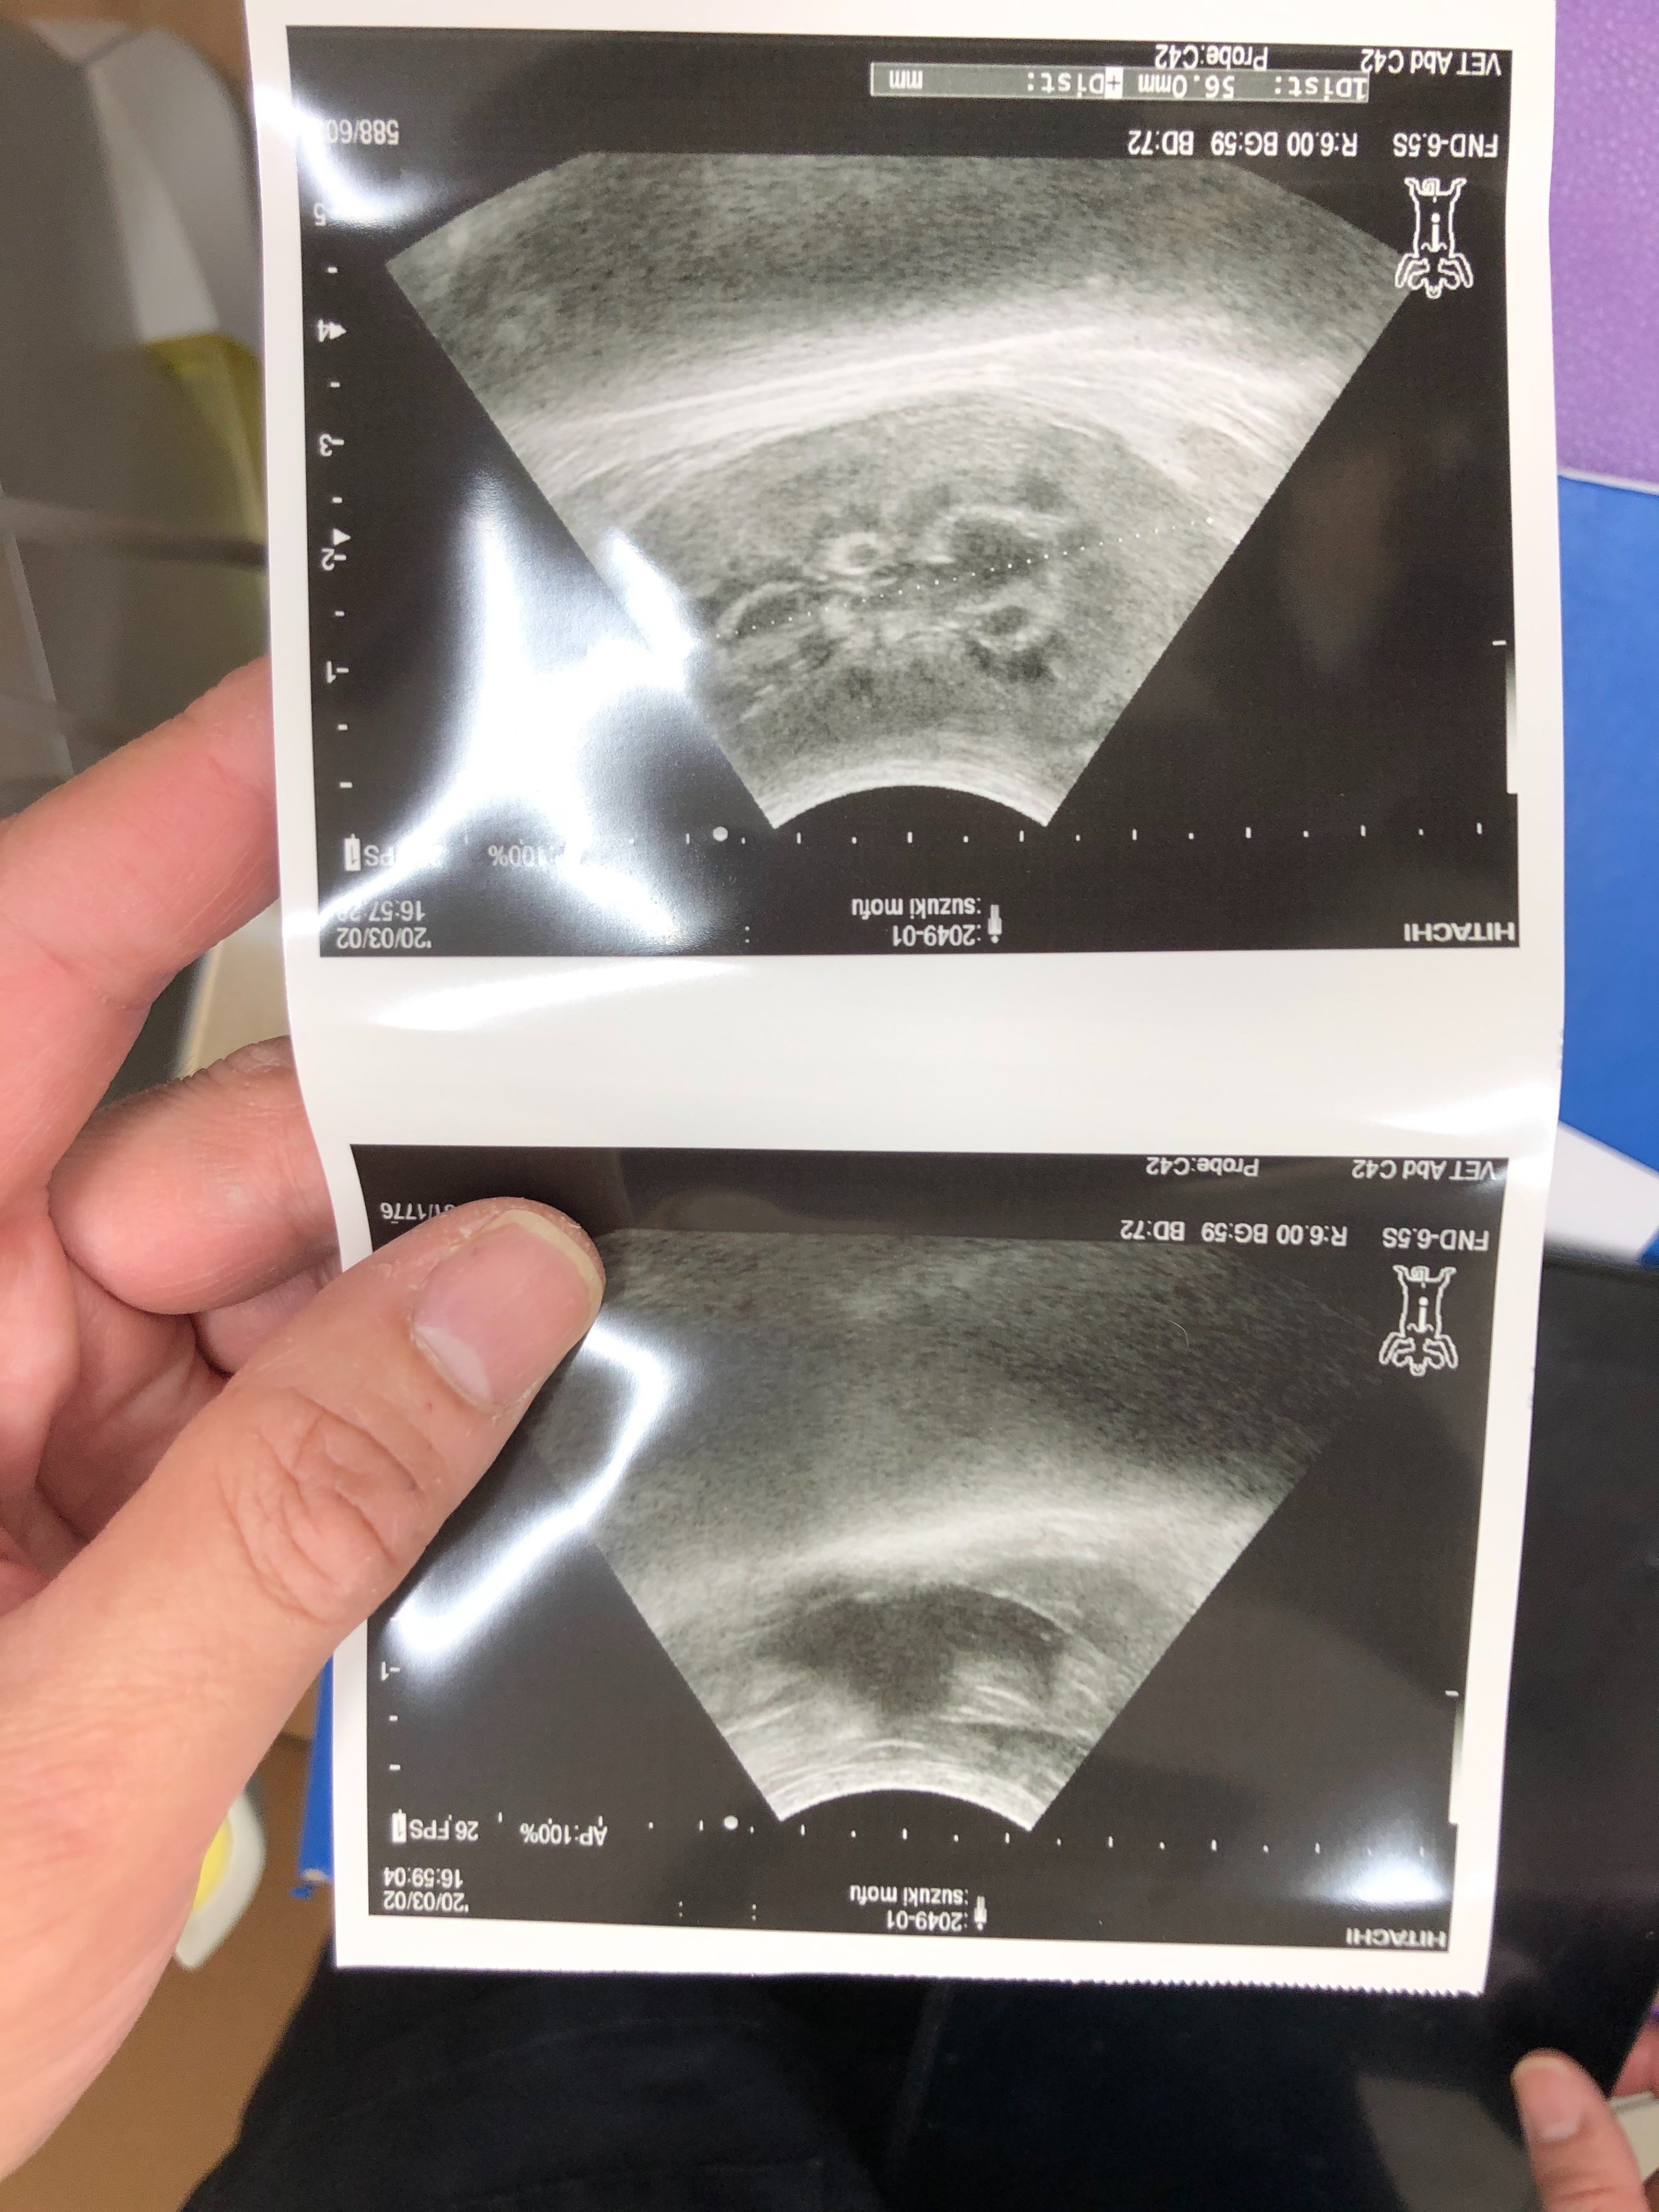

↑(エコー上部:腎臓にFIPの特徴である白い影、エコー下部:少量の腹水あり)